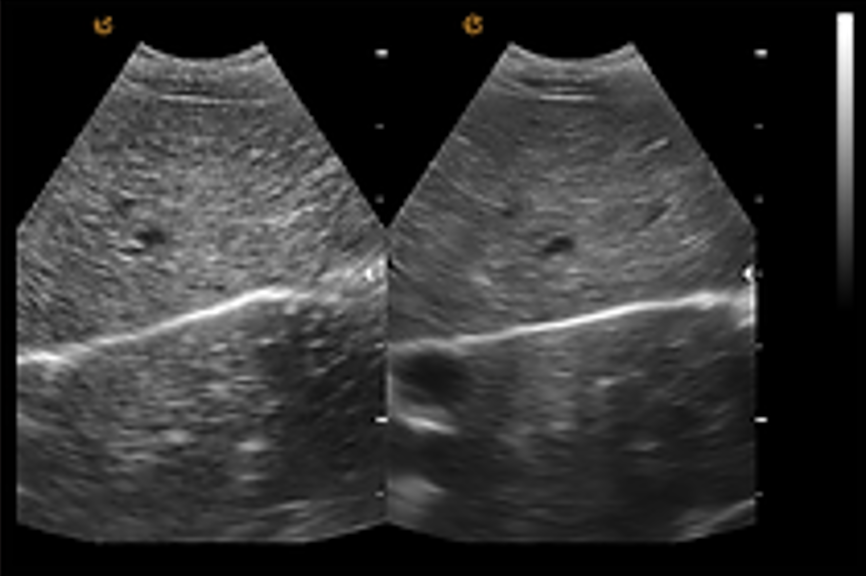

เทคโนโลยีลดจุดรบกวน ePure + เทคโนโลยีลดจุดรบกวน (Speckle Reduction Technology) เป็นเทคโนโลยีที่ช่วยลดสัญญาณรบกวนที่เกิดจากคลื่นสะท้อน (echo) ได้อย่างมีประสิทธิภาพ พร้อมทั้งปรับความสม่ำเสมอของชั้นเนื้อเยื่อต่างๆ ให้เหมาะสม ส่งผลให้ได้ภาพคุณภาพสูงที่มีความคมชัดและขอบภาพที่ชัดเจน |

eSCI การสร้างภาพเชิงพื้นที่แบบผสม การถ่ายภาพอัลตราซาวด์จากหลายมุมมองในระนาบเดียวกันเพื่อสร้างเป็นภาพที่ประกอบขึ้นจากหลายภาพ (tomographic ultrasound images) ผลลัพธ์ที่ได้จะช่วยลดจุดรบกวน (speckle) เสียงรบกวน (clutter) และข้อผิดพลาดทางเสียงสะท้อน (acoustic artifacts) อย่างมีนัยสำคัญ |

การระบุตำแหน่งร่างกายสัตว์และบันทึก ระบบระบุตำแหน่งร่างกายสัตว์ที่หลากหลาย ช่วยให้สัตวแพทย์สามารถเลือกและทำเครื่องหมายได้ทันที เพื่อเพิ่มความสะดวกและประสิทธิภาพในการวินิจฉัย ชุดซอฟต์แวร์สัตวแพทย์ระดับมืออาชีพ จากประสบการณ์ความต้องการของสัตวแพทย์ทั่วโลก EMP ได้พัฒนาชุดซอฟต์แวร์สำหรับสัตวแพทย์โดยเฉพาะ โดยมุ่งเน้นความต้องการจากทางคลินิกที่มากที่สุดในบริเวณช่องท้องและพื้นผิว ตั้งแต่การตั้งค่าพารามิเตอร์ล่วงหน้าไปจนถึงชุดเครื่องมือวัดสำหรับสัตว์ประเภทต่างๆ เพื่อมอบระบบการวินิจฉัยที่เชื่อถือได้ให้กับสัตวแพทย์ ชุดซอฟต์แวร์สูติศาสตร์สัตวแพทย์ ชุดซอฟต์แวร์สูติศาสตร์สำหรับสัตวแพทย์ที่ช่วยคาดการณ์วันคลอดและประเมินสภาพร่างกายของลูกสัตว์ได้อย่างแม่นยำตามประเภทของสัตว์แต่ละชนิด. การสร้างภาพขยาย ชุดหัวตรวจอาร์เรย์นูนรองรับการสร้างภาพขยาย (Extended Imaging) ซึ่งขยายขอบเขตการสแกนของหัวตรวจได้อย่างมีประสิทธิภาพ รองรับการใช้งานในด้านสูติศาสตร์, นรีเวชวิทยา, และการวินิจฉัยที่มีขนาดใหญ่ รวมถึงการสังเกตสภาพของเนื้อเยื่อที่มีการบาดเจ็บและเนื้อเยื่อสำคัญ |

ชุดหัวตรวจอาร์เรย์นูนรองรับการสร้างภาพขยาย (Extended Imaging) ซึ่งขยายขอบเขตการสแกนของหัวตรวจได้อย่างมีประสิทธิภาพ รองรับการใช้งานในด้านสูติศาสตร์, นรีเวชวิทยา, และการวินิจฉัยที่มีขนาดใหญ่ รวมถึงการสังเกตสภาพของเนื้อเยื่อที่มีการบาดเจ็บและเนื้อเยื่อสำคัญ